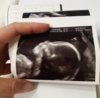

Podobno dziewczynka :)

21+2 tc